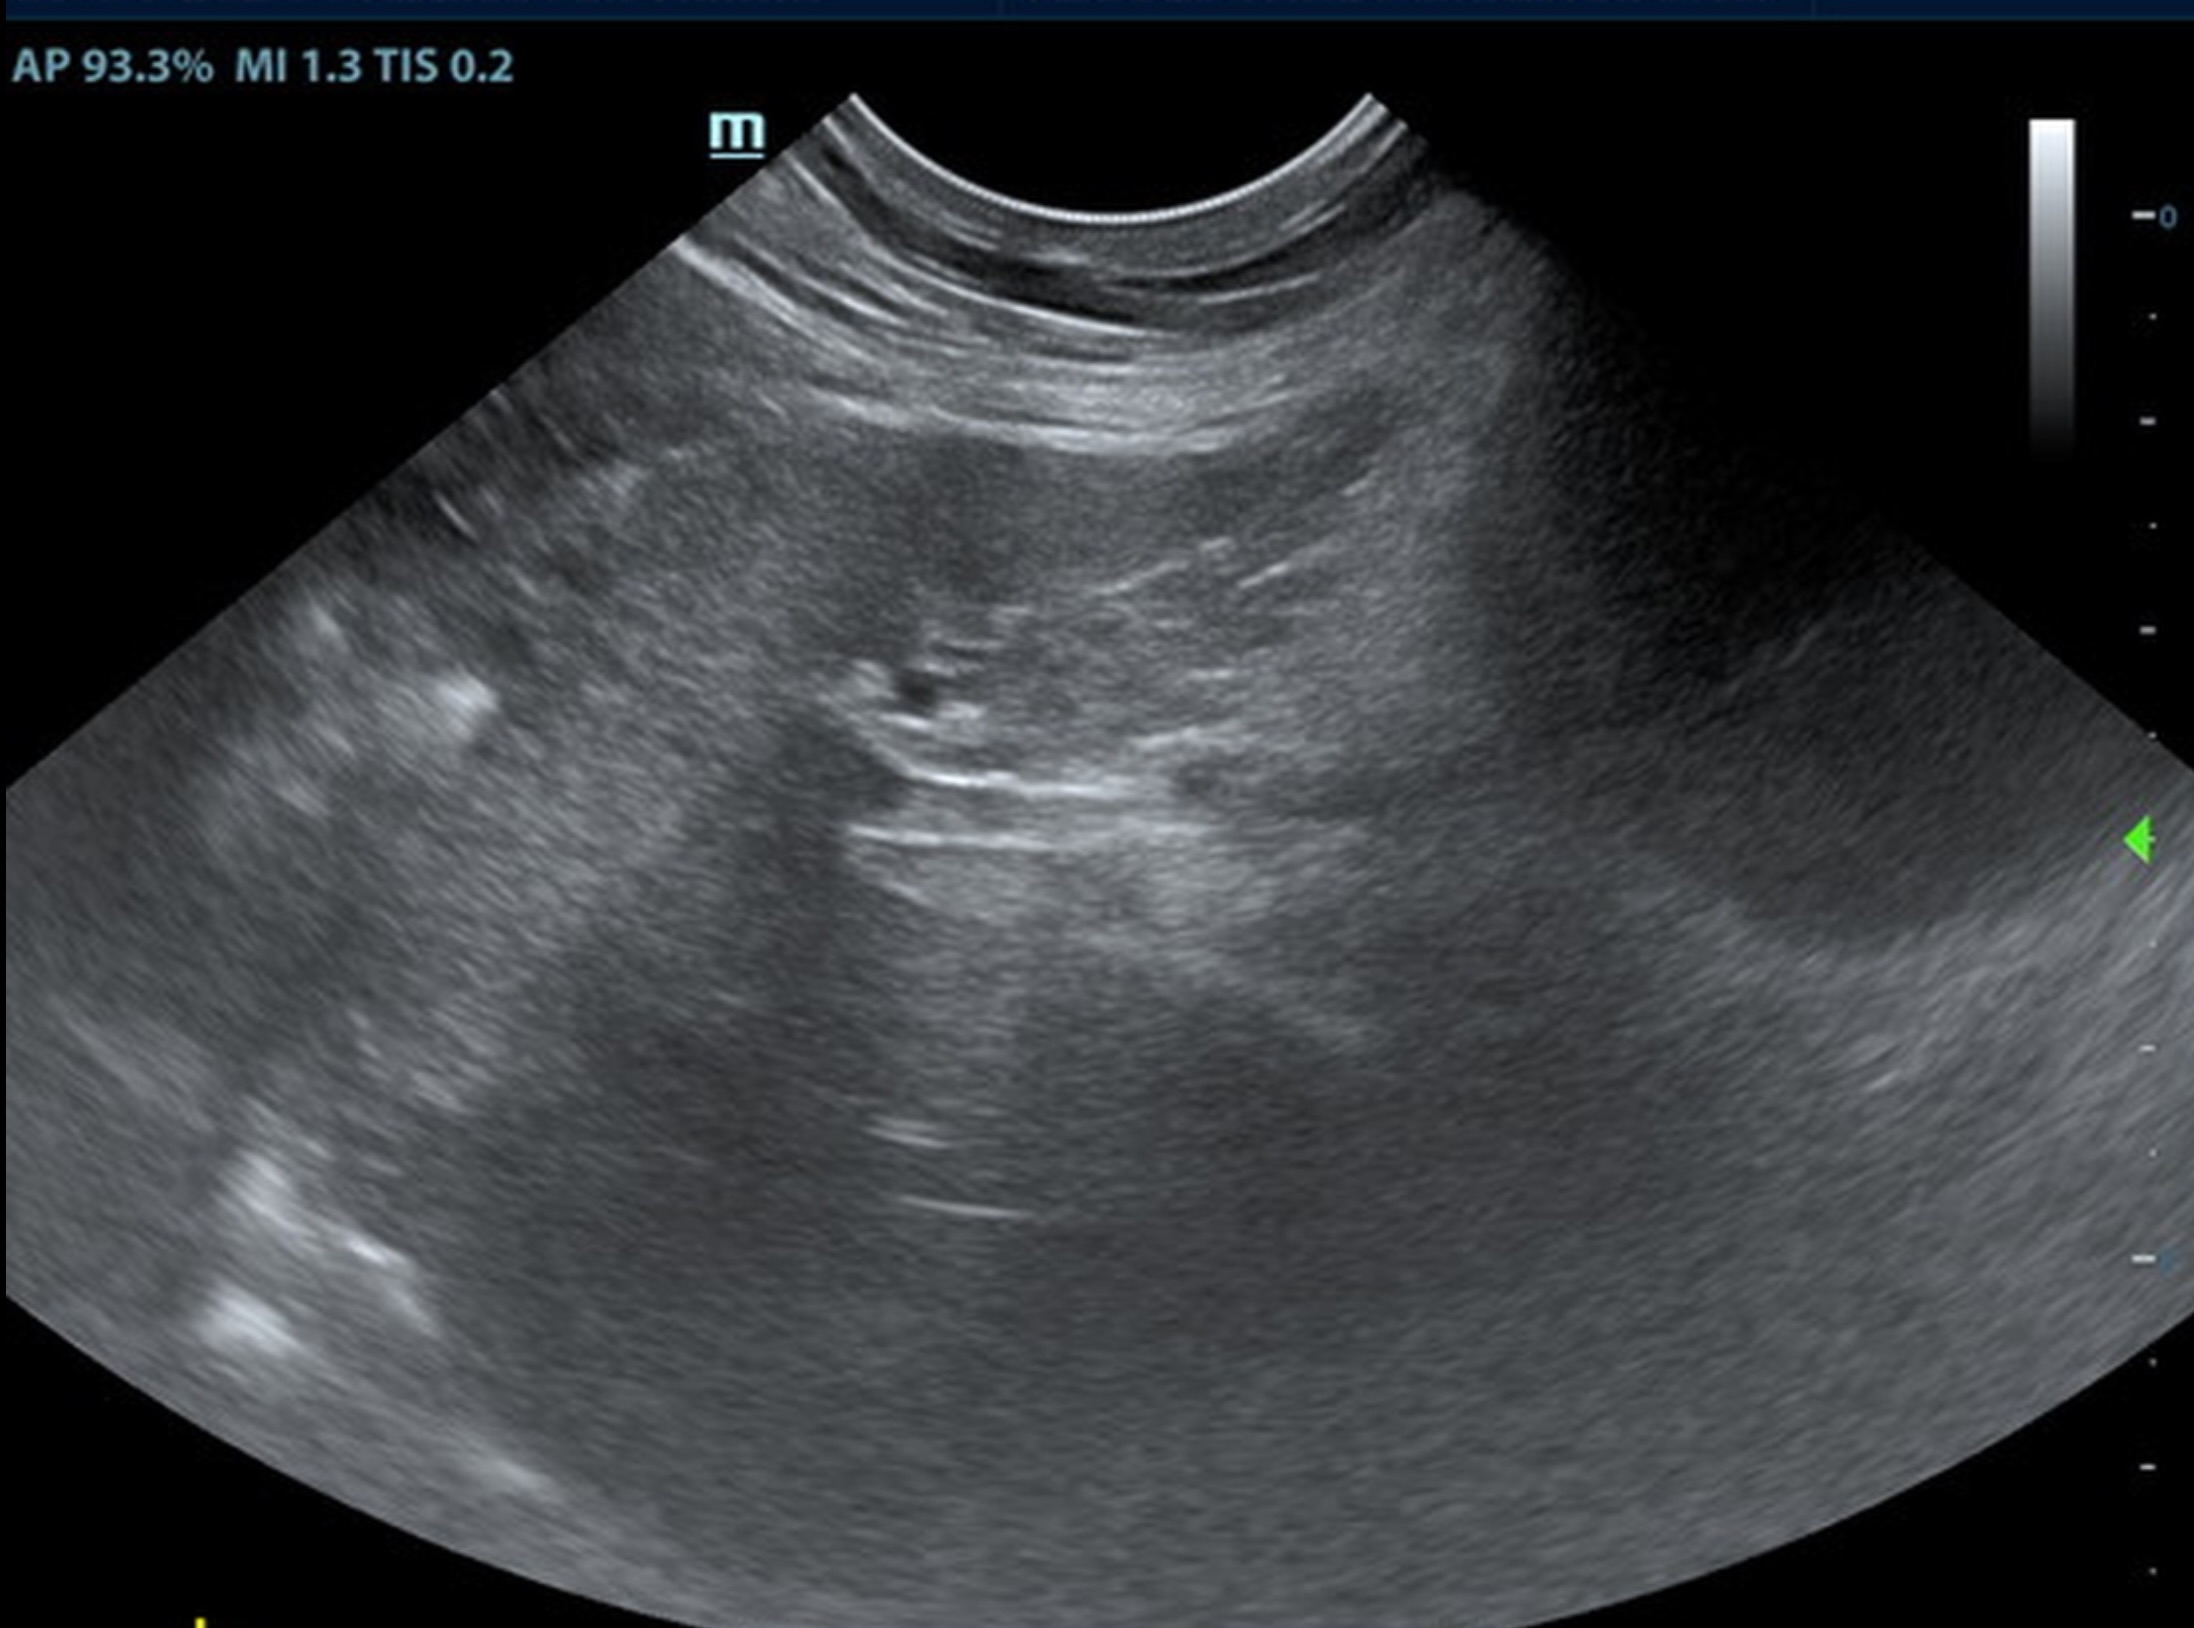

Renal: some age-related loss of curvilinear patterns regarding the capsule and C/M junction. The cortices presented largely uniform texture with some increased echogenicity expected for his age patient.

• Age related renal changes.